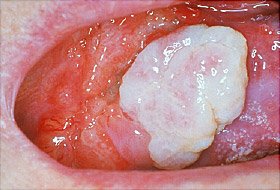

- fehér, piros, fehér, vagy vörös foltok vagy a szád, vagy az ajkak

- Duzzanat/thickenings, csomók, vagy dudorok, durva foltok/héját/vagy erodált területek, a száj, az íny, vagy más területeken belül a száját

- A fejlesztés bársonyos fehér, piros, vagy foltos (fehér, vörös) foltok a szájban